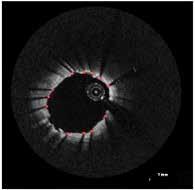

BIOMECHANICS OF ATHEROSCLEROSIS

COLLABORATION ON THREE NIH R01 STUDIES

1. Acquire Imaging Data

4. Identify Status

Acquire Undeployed Stent

6. Remove Stent from Lumen 5. Deform undeployed stent

3. Contour Lumen

7. Compute WSS